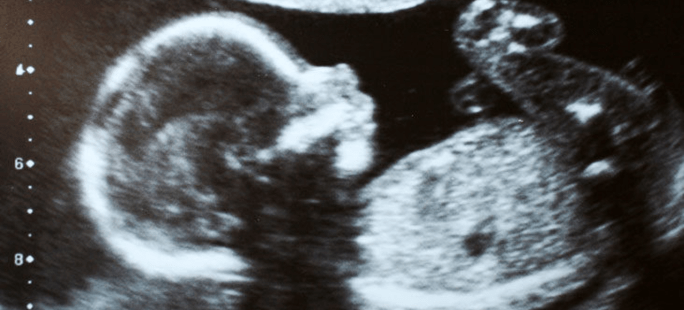

My 15th week of pregnancy another ultrasound showed us our daughter inside me. “The ghost in the machine,” my husband had said quietly. By then we’d decided raising a child — ill from birth who’d likely never survive to adulthood — was beyond our financial, parental, and emotional capabilities.